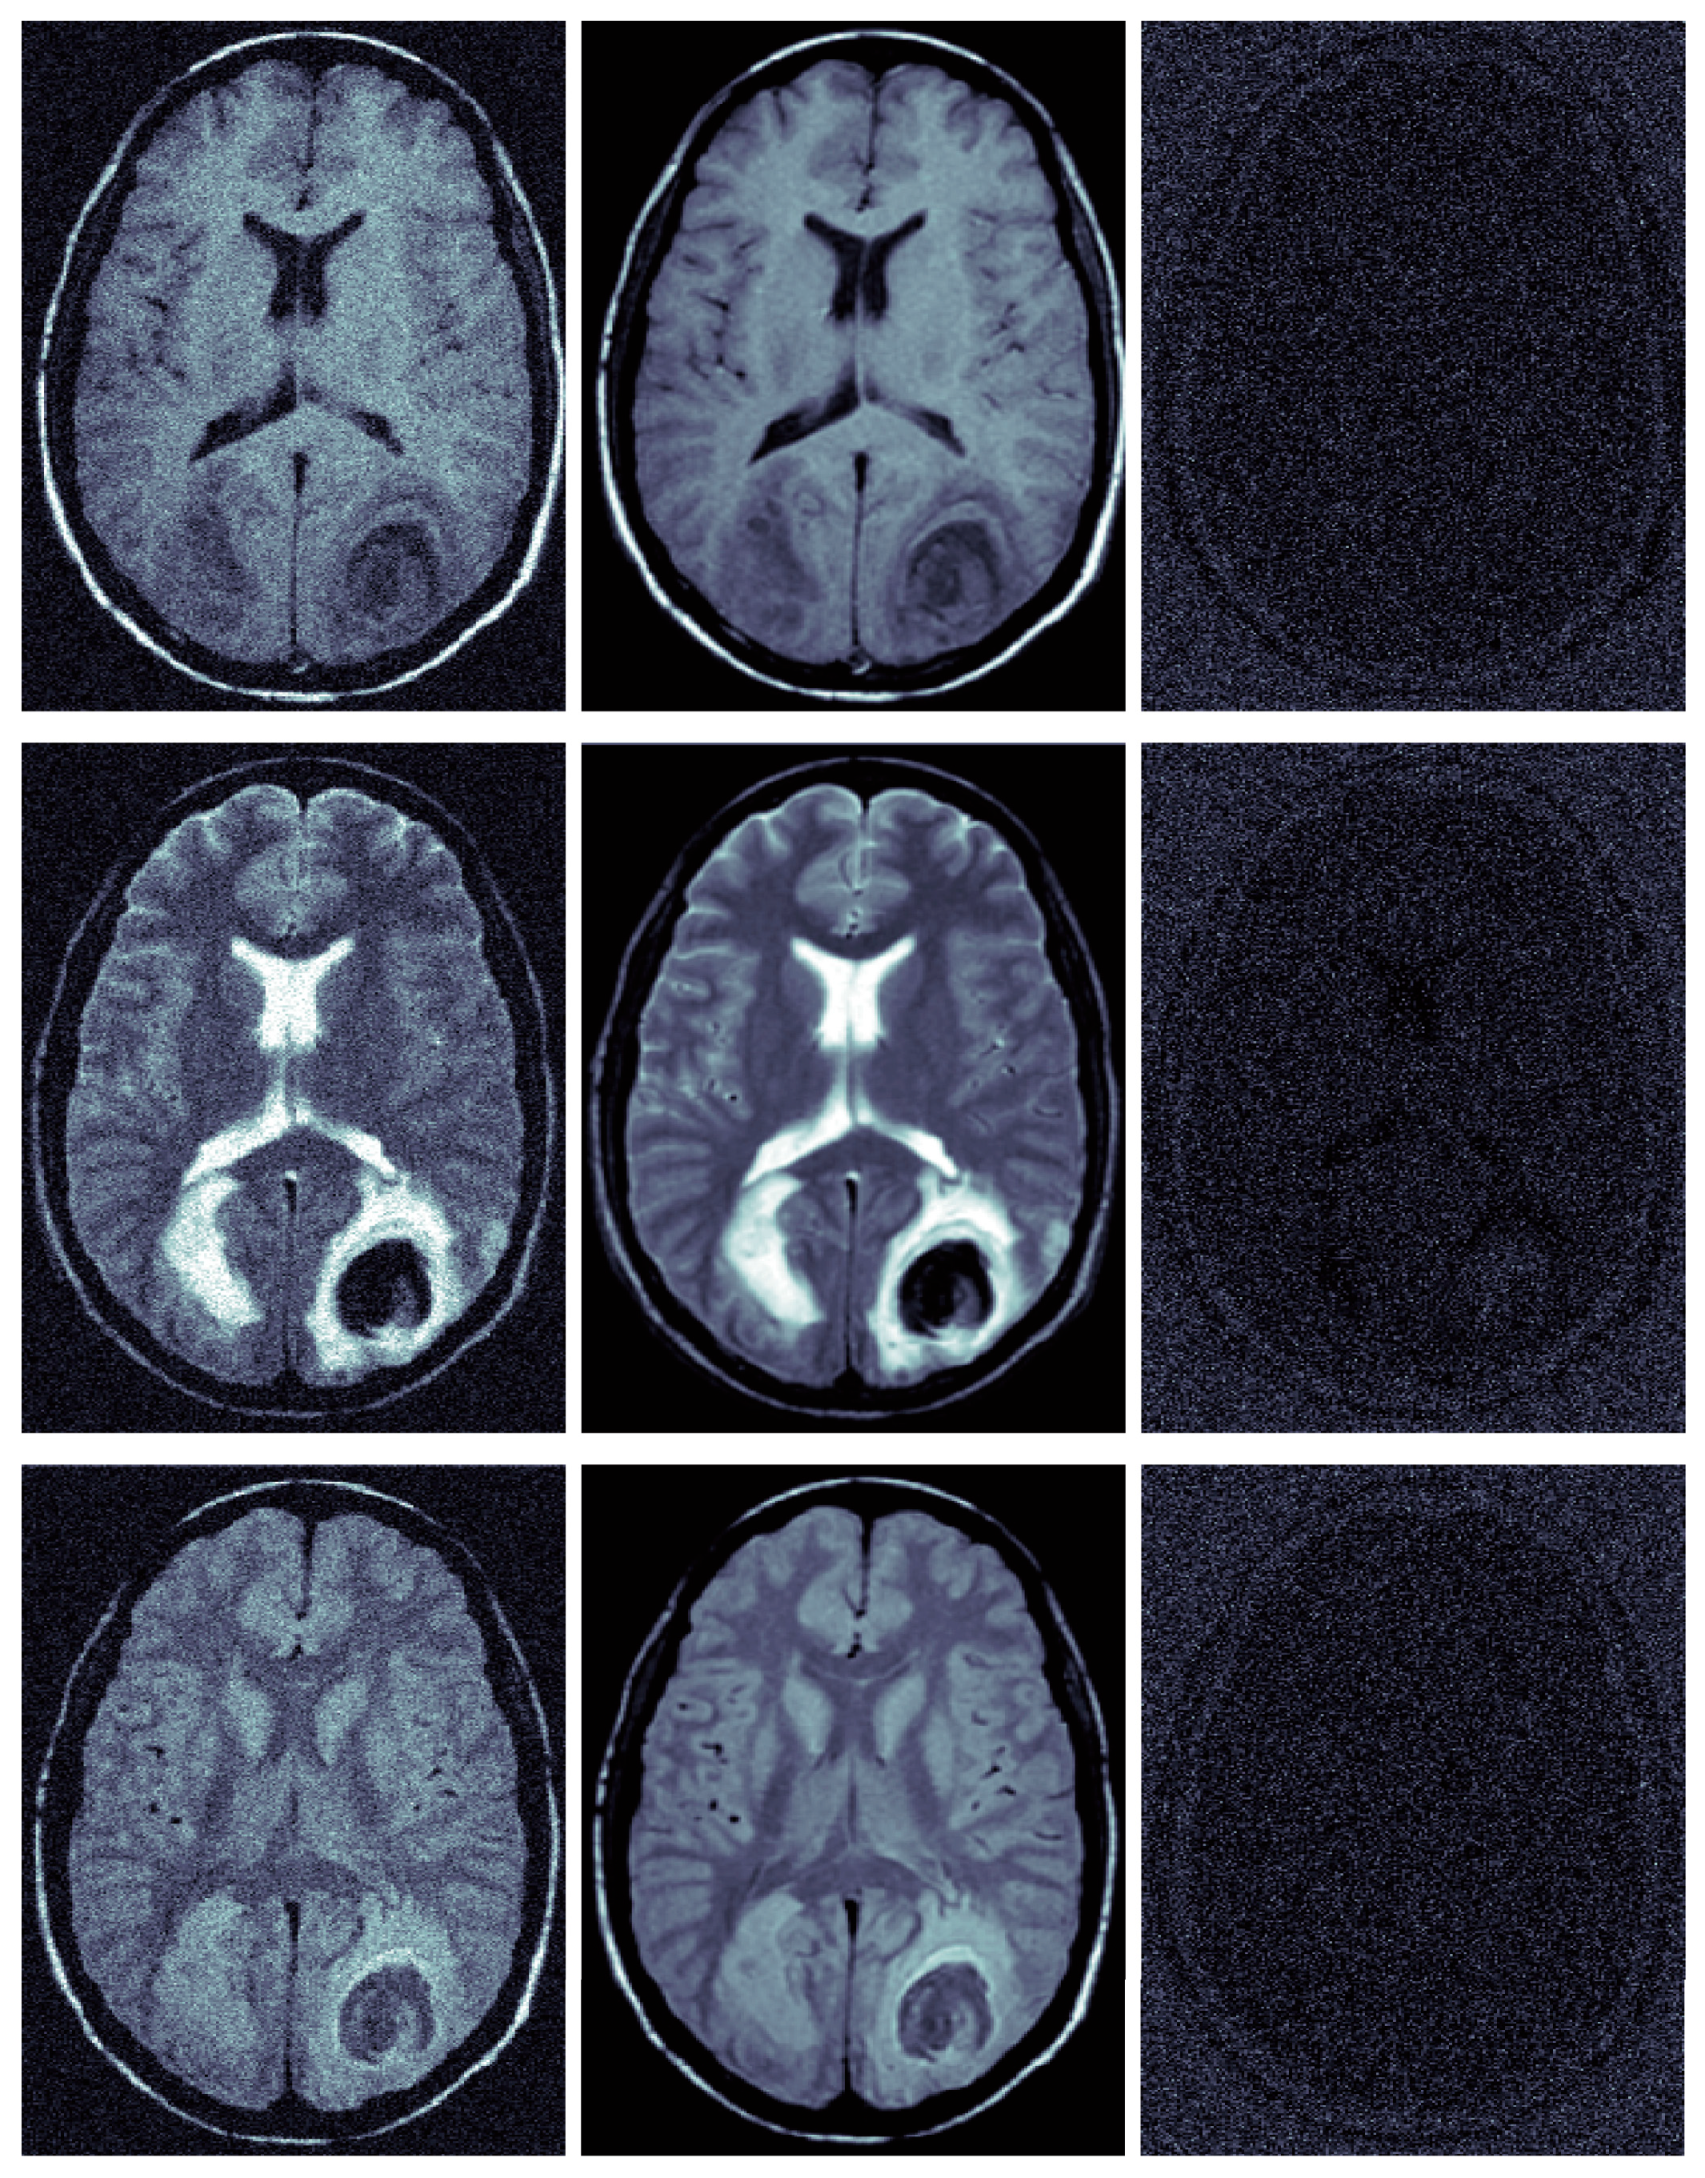

The experimental results of the proposed method show clear advantages over the previous state-of-the-art algorithms. To use absolute clean MRIs as numerical references, we used the SBD, which is synthetic data, and may not be realistic enough. To prove the effectiveness of the proposed algorithm in removing noise in real clinical MRIs and avoid the contingency of denoising results at the same time, we also conducted further experiments using real clinical MR brain datasets [6,30]. A large number of experiments based on real clinical datasets showed that denoised MRIs are clearer than original real images, and residual images have no anatomical structure. Figure 9 is one of the experimental results with three modalities. Table 5 shows the average denoising results obtained from real brain datasets (113 2D-T1w, 184 2D-T2w, 136 2D-PDw, 581 3D-T1w, 578 3D-T2w, 578 3D-PDw).

Figure 9.

Real clinical images denoising examples (the 13th slice of brain tumor MRI was taken from a 22-year-old male brain tumor patient in the real clinical data set of Harvard University). From top to bottom, the left column represents real T1w, real T2w, and the real PDw; the middle column is the corresponding filtered images; the right column is the corresponding residual images (removed Rician noise).